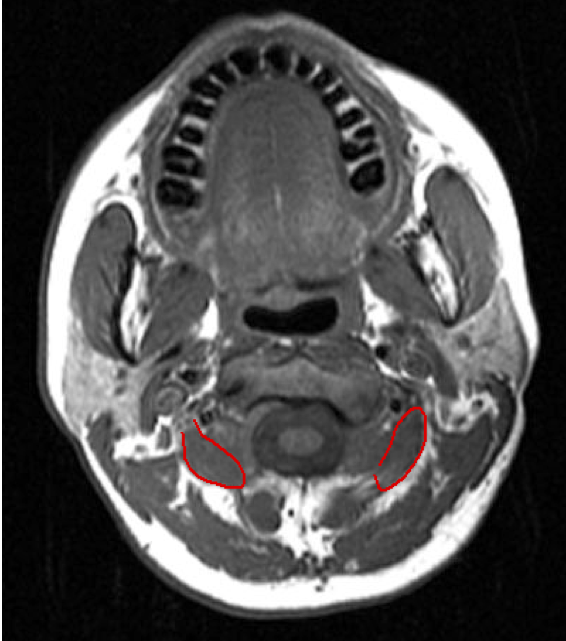

ACCURACY OF LOCALIZATION - SCALENES

ACCURACY OF LOCALIZATION LEVATOR SCAPULAE

- Muscles deep

- Not easily identified by surface landmarks

- Not palpable on examination

Accuracy of Muscle Localization

-

Planning of muscles to inject - determination of active muscles

Localization of endplates

- Less problems with diffusion